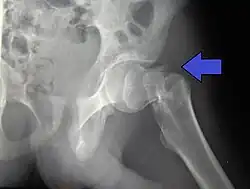

Nonunion, failure of the fracture to heal, is common in fractures of the neck of the femur, but much more rare with other types of hip fracture. Avascular necrosis of the femoral head occurs frequently (20%) in intracapsular hip fractures, because the blood supply is interrupted.[5]

In elderly patients with displaced or intracapsular fractures surgeons may decide to perform a hemiarthroplasty, replacing the broken part of the bone with a metal implant.[39] However, in elderly people who are medically well and still active, a total hip replacement may be indicated. Independently mobile older adults with hip fractures may benefit from a total hip replacement instead of hemiarthroplasty.[40]